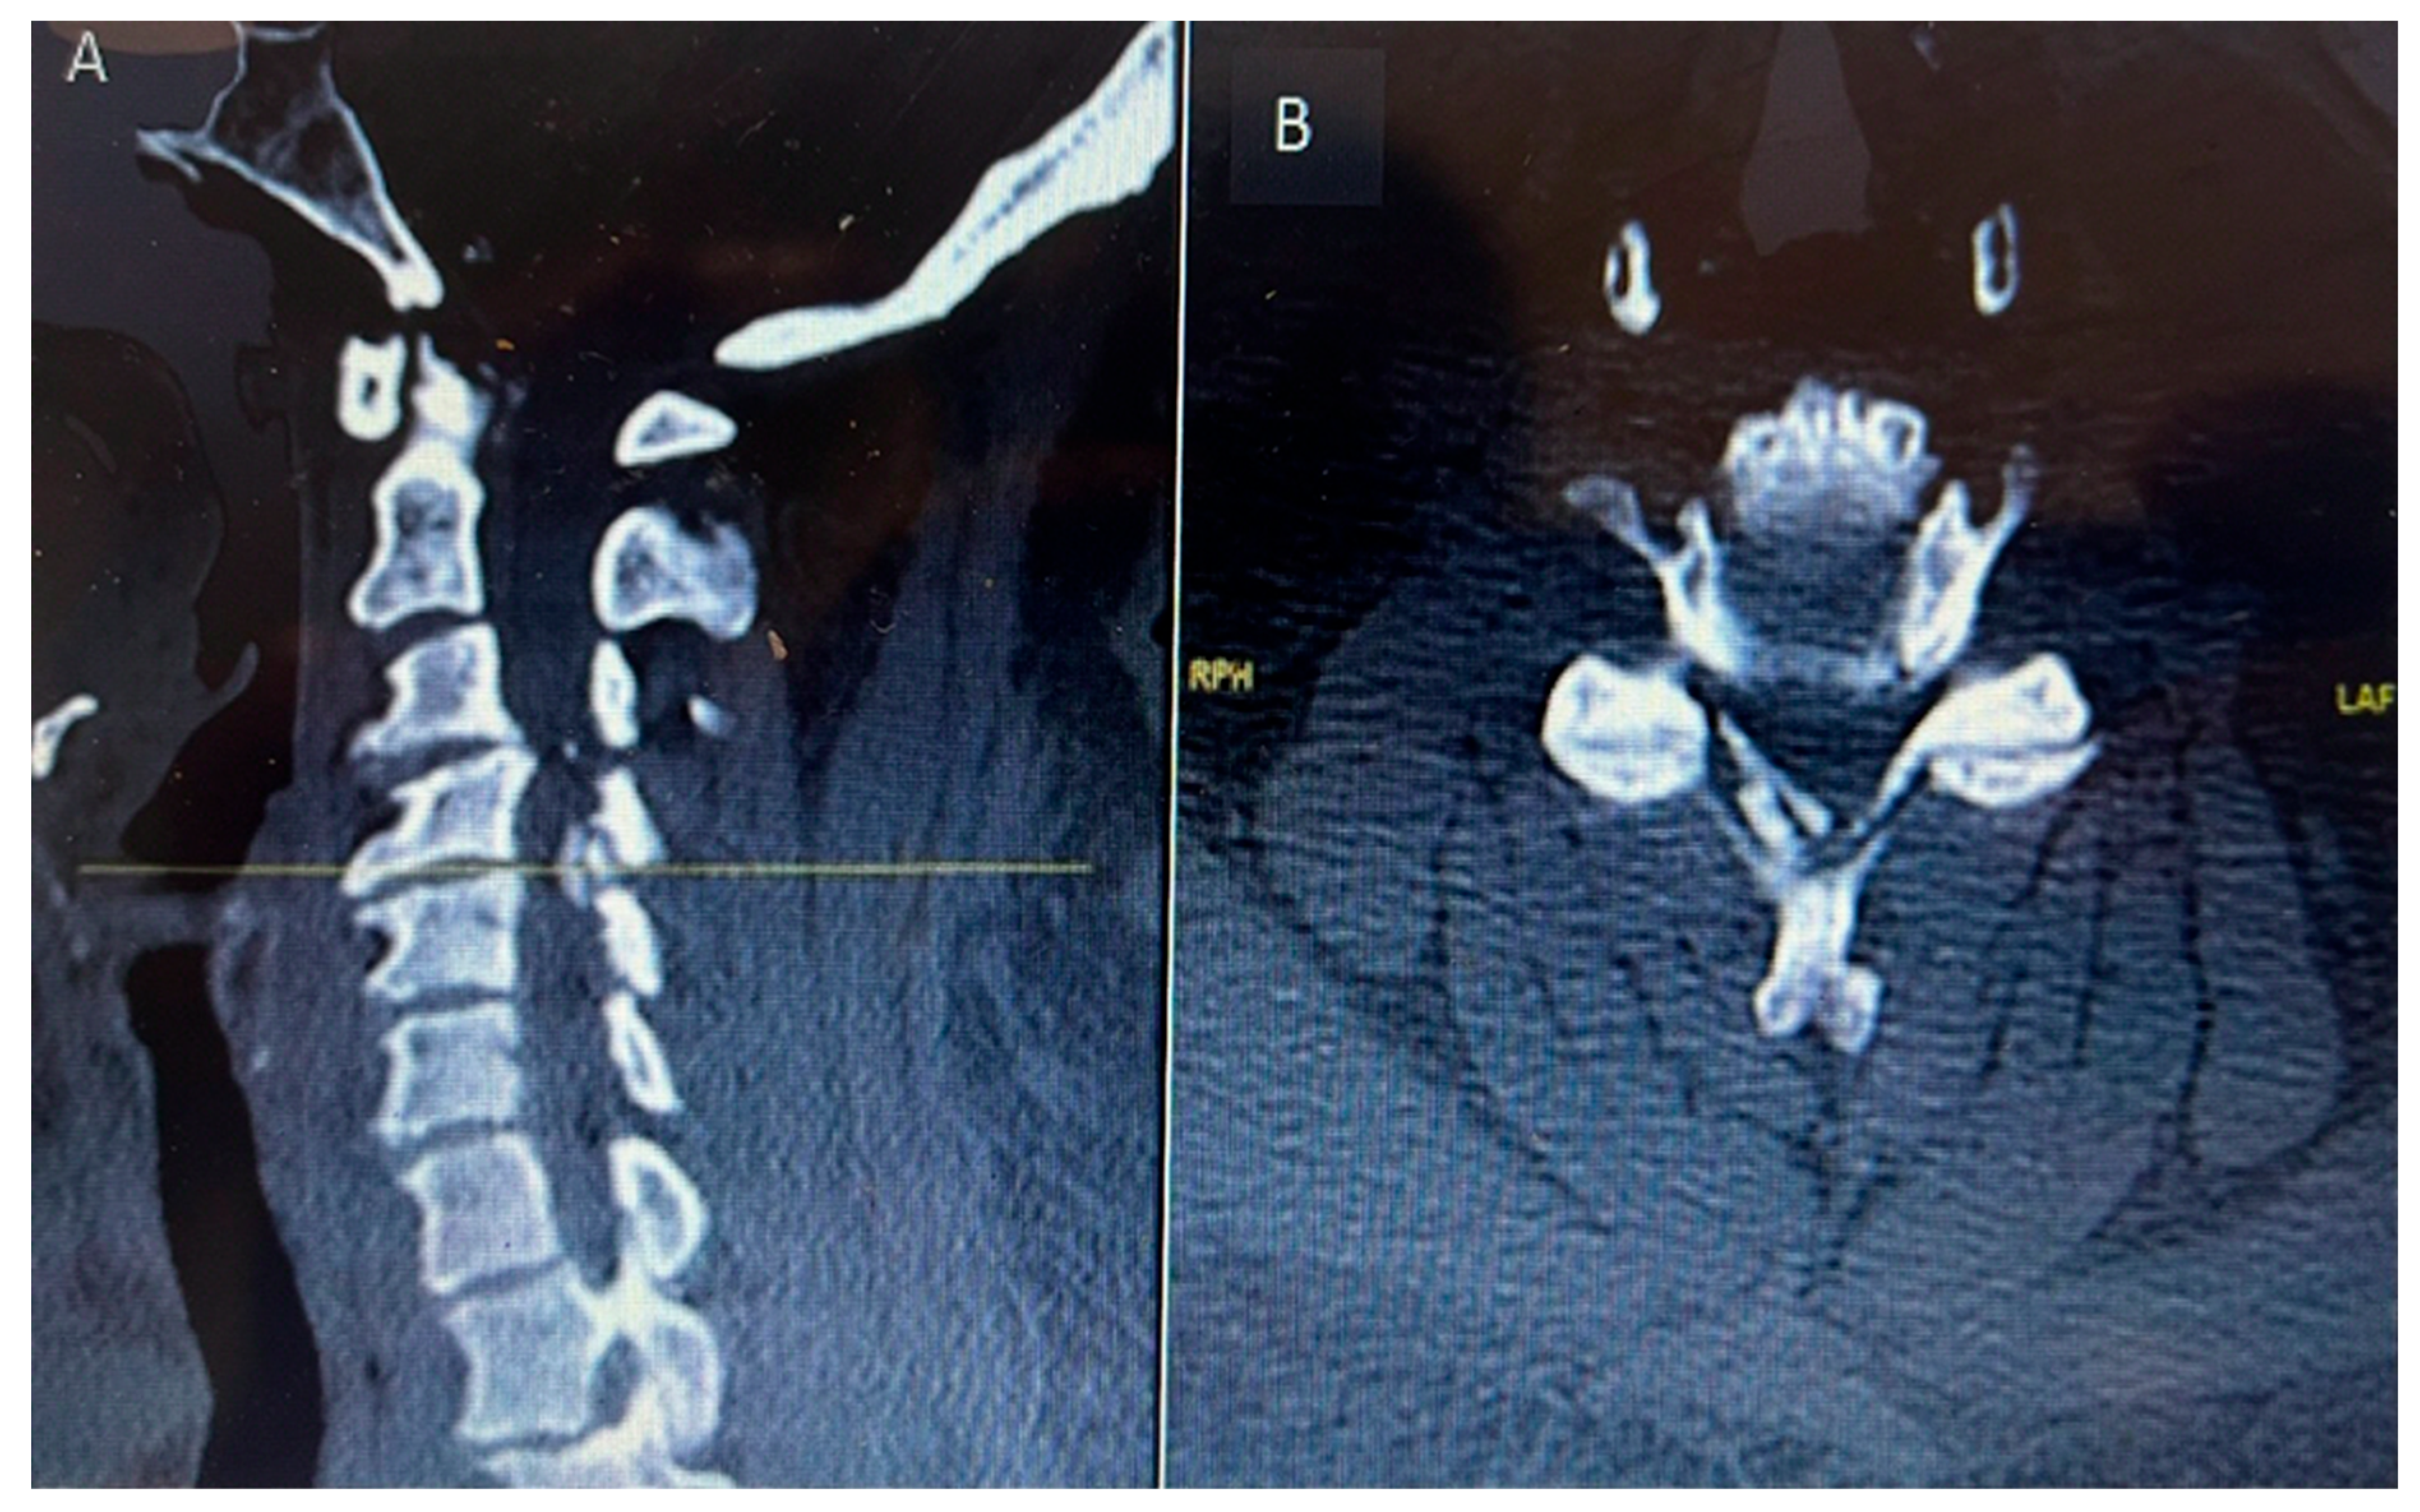

CT C Spine: Ossification of the right-side ligamentum flavum noted at C4/C5 and C5/C6 levels, with associated spinal canal narrowing, more severe at C4/C5.

Figure 1. Preoperative sagittal (A) and axial (B) CT cervical spine showing calcific deposit at the cervical 4 level causing spinal stenosis.

MRI Whole Spine: Severe central canal narrowing causing compression of the spinal cord with myelomalacia at C4/C5 level, with mild retrolisthesis at C4 over C5, thickening of the posterior longitudinal ligament, and ligamentum flavum hypertrophy. Various degrees of central canal narrowing and neural foraminal narrowing were noted at C3/C4, C4/C5, C5/C6, and C6/C7 levels, with additional findings including a small synovial cyst at C6/C7.

Figure 2. Preoperative MRI cervical spine T2 weighted sagittal (A) and axial (B) showing cord compression posteriorly with cord signal change at cervical 4 level.